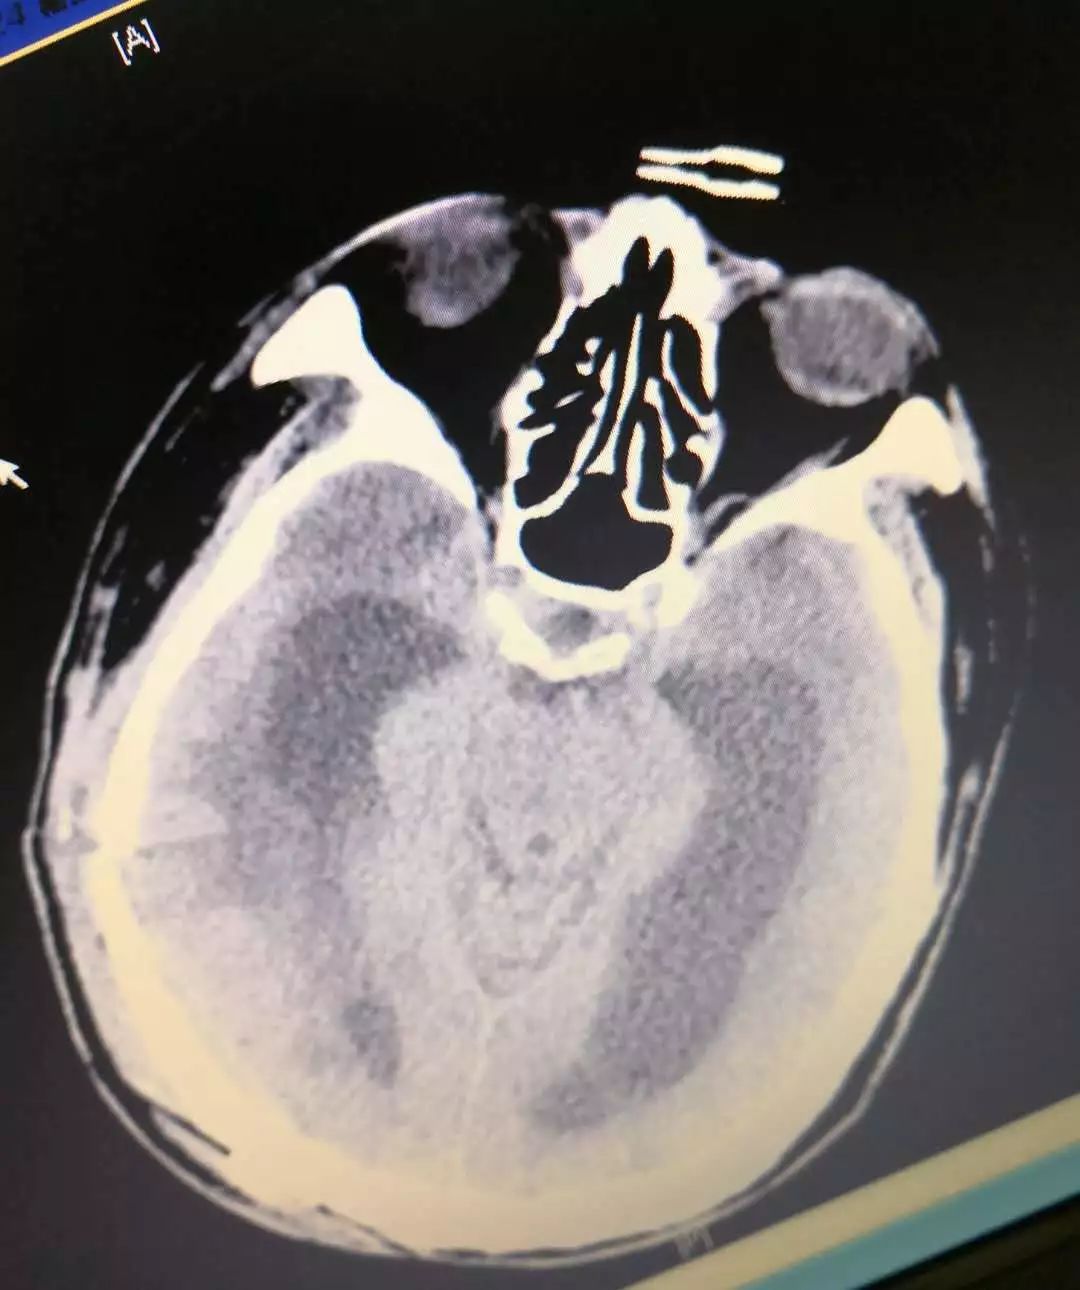

临床上我们通常依据临床症状和体征,再结合影像学资料(CT和MRI)及腰穿就可以明确诊断脑积水。脑积水在CT和MRI上主要表现为脑室扩大而皮质萎缩不明显。

CT提示侧脑室扩大